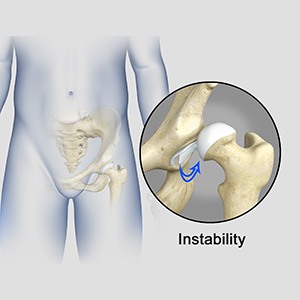

Hip Instability

The hip plays an important role in supporting your upper body weight while standing, walking and running, and hip stability is crucial for these functions. The femur (thighbone) and acetabulum (socket-shaped region of the pelvis) join to form the hip joint, while the labrum (rim of tissue that seals the hip joint) and the ligaments lining the hip...